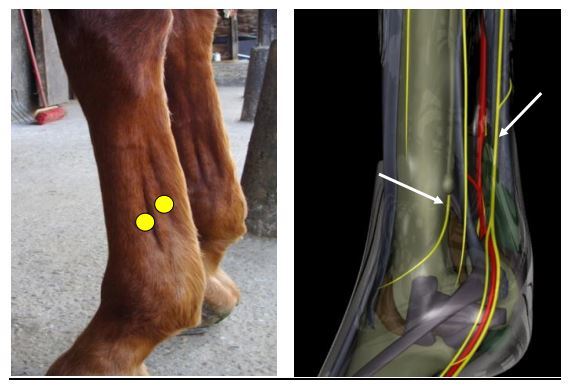

How do you do a Palmar or plantar abaxial sesamoid nerve block (ASNB)?

Palpate the neurovascular bundle at the level of the base of the proximal sesamoid bones. The palmar digital nerve lies most palmar (structures from dorsal to palmar: vein – artery- nerve). AIM DISTALLY